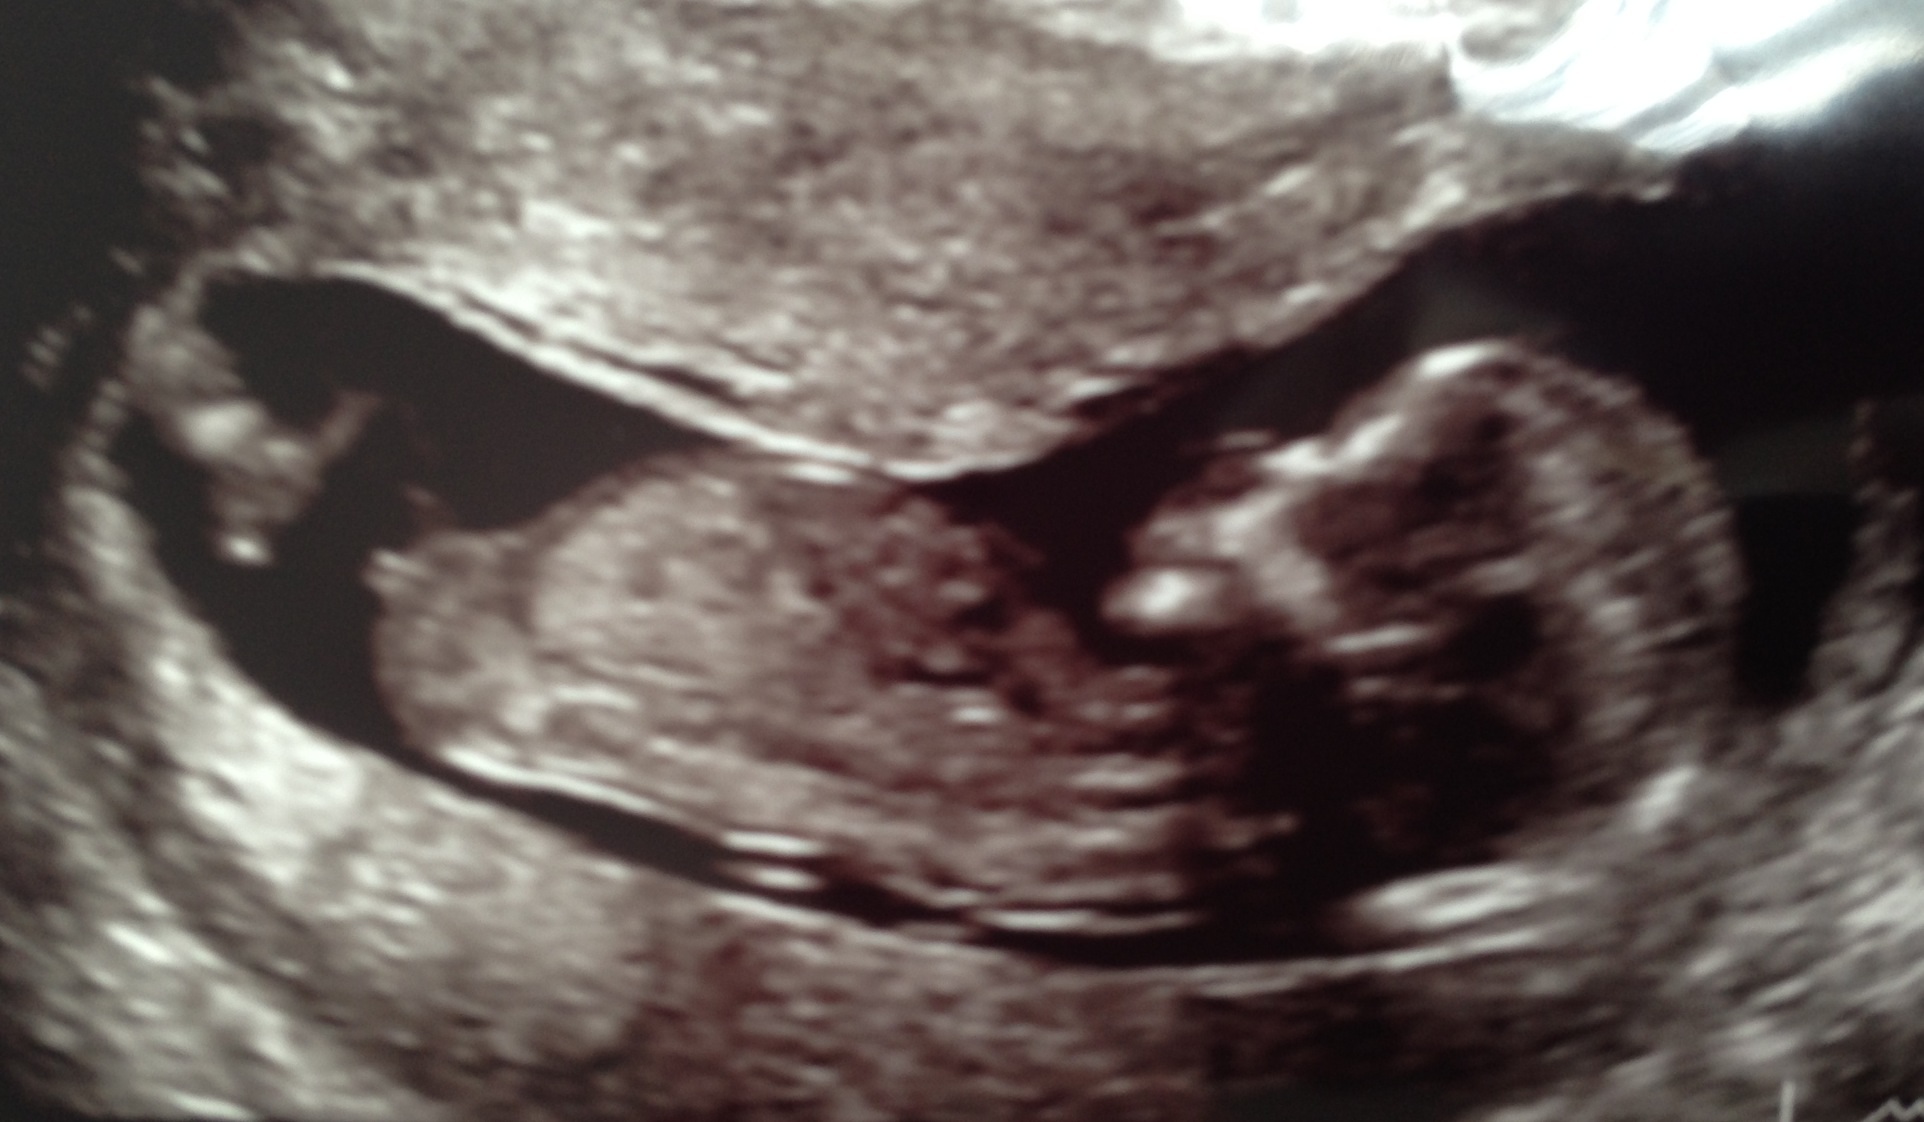

If that top pic is showing the nub, I'd have to say girl :)

Baby was upside down so I've just flipped it over? Don't know if that would change angle of nub??